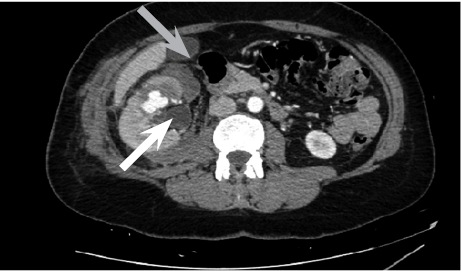

Cause of hematuria had to be determined, therefore urgent contrast enhanced computed tomography was performed (Figure 2) – contrast extravazation was found on the lower third of the right kidney (area of surgery), along with subcapsular hemathoma. Right hydroureteronephrosis and fluid in pelvis were observed. Blood clots and a small amount of contrast in the bladder were seen.

Figure 2. Contrast extravazation was found on the lower third of the right kidney (white arrow), subcapsular hemathoma (grey arrow)